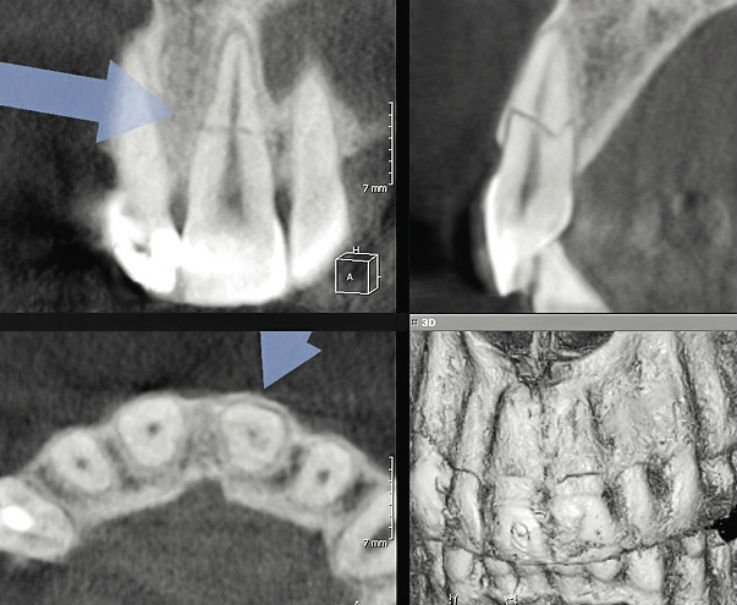

Рентгеновские снимки кариеса корня зуба

Раздел: Визуальные уроки